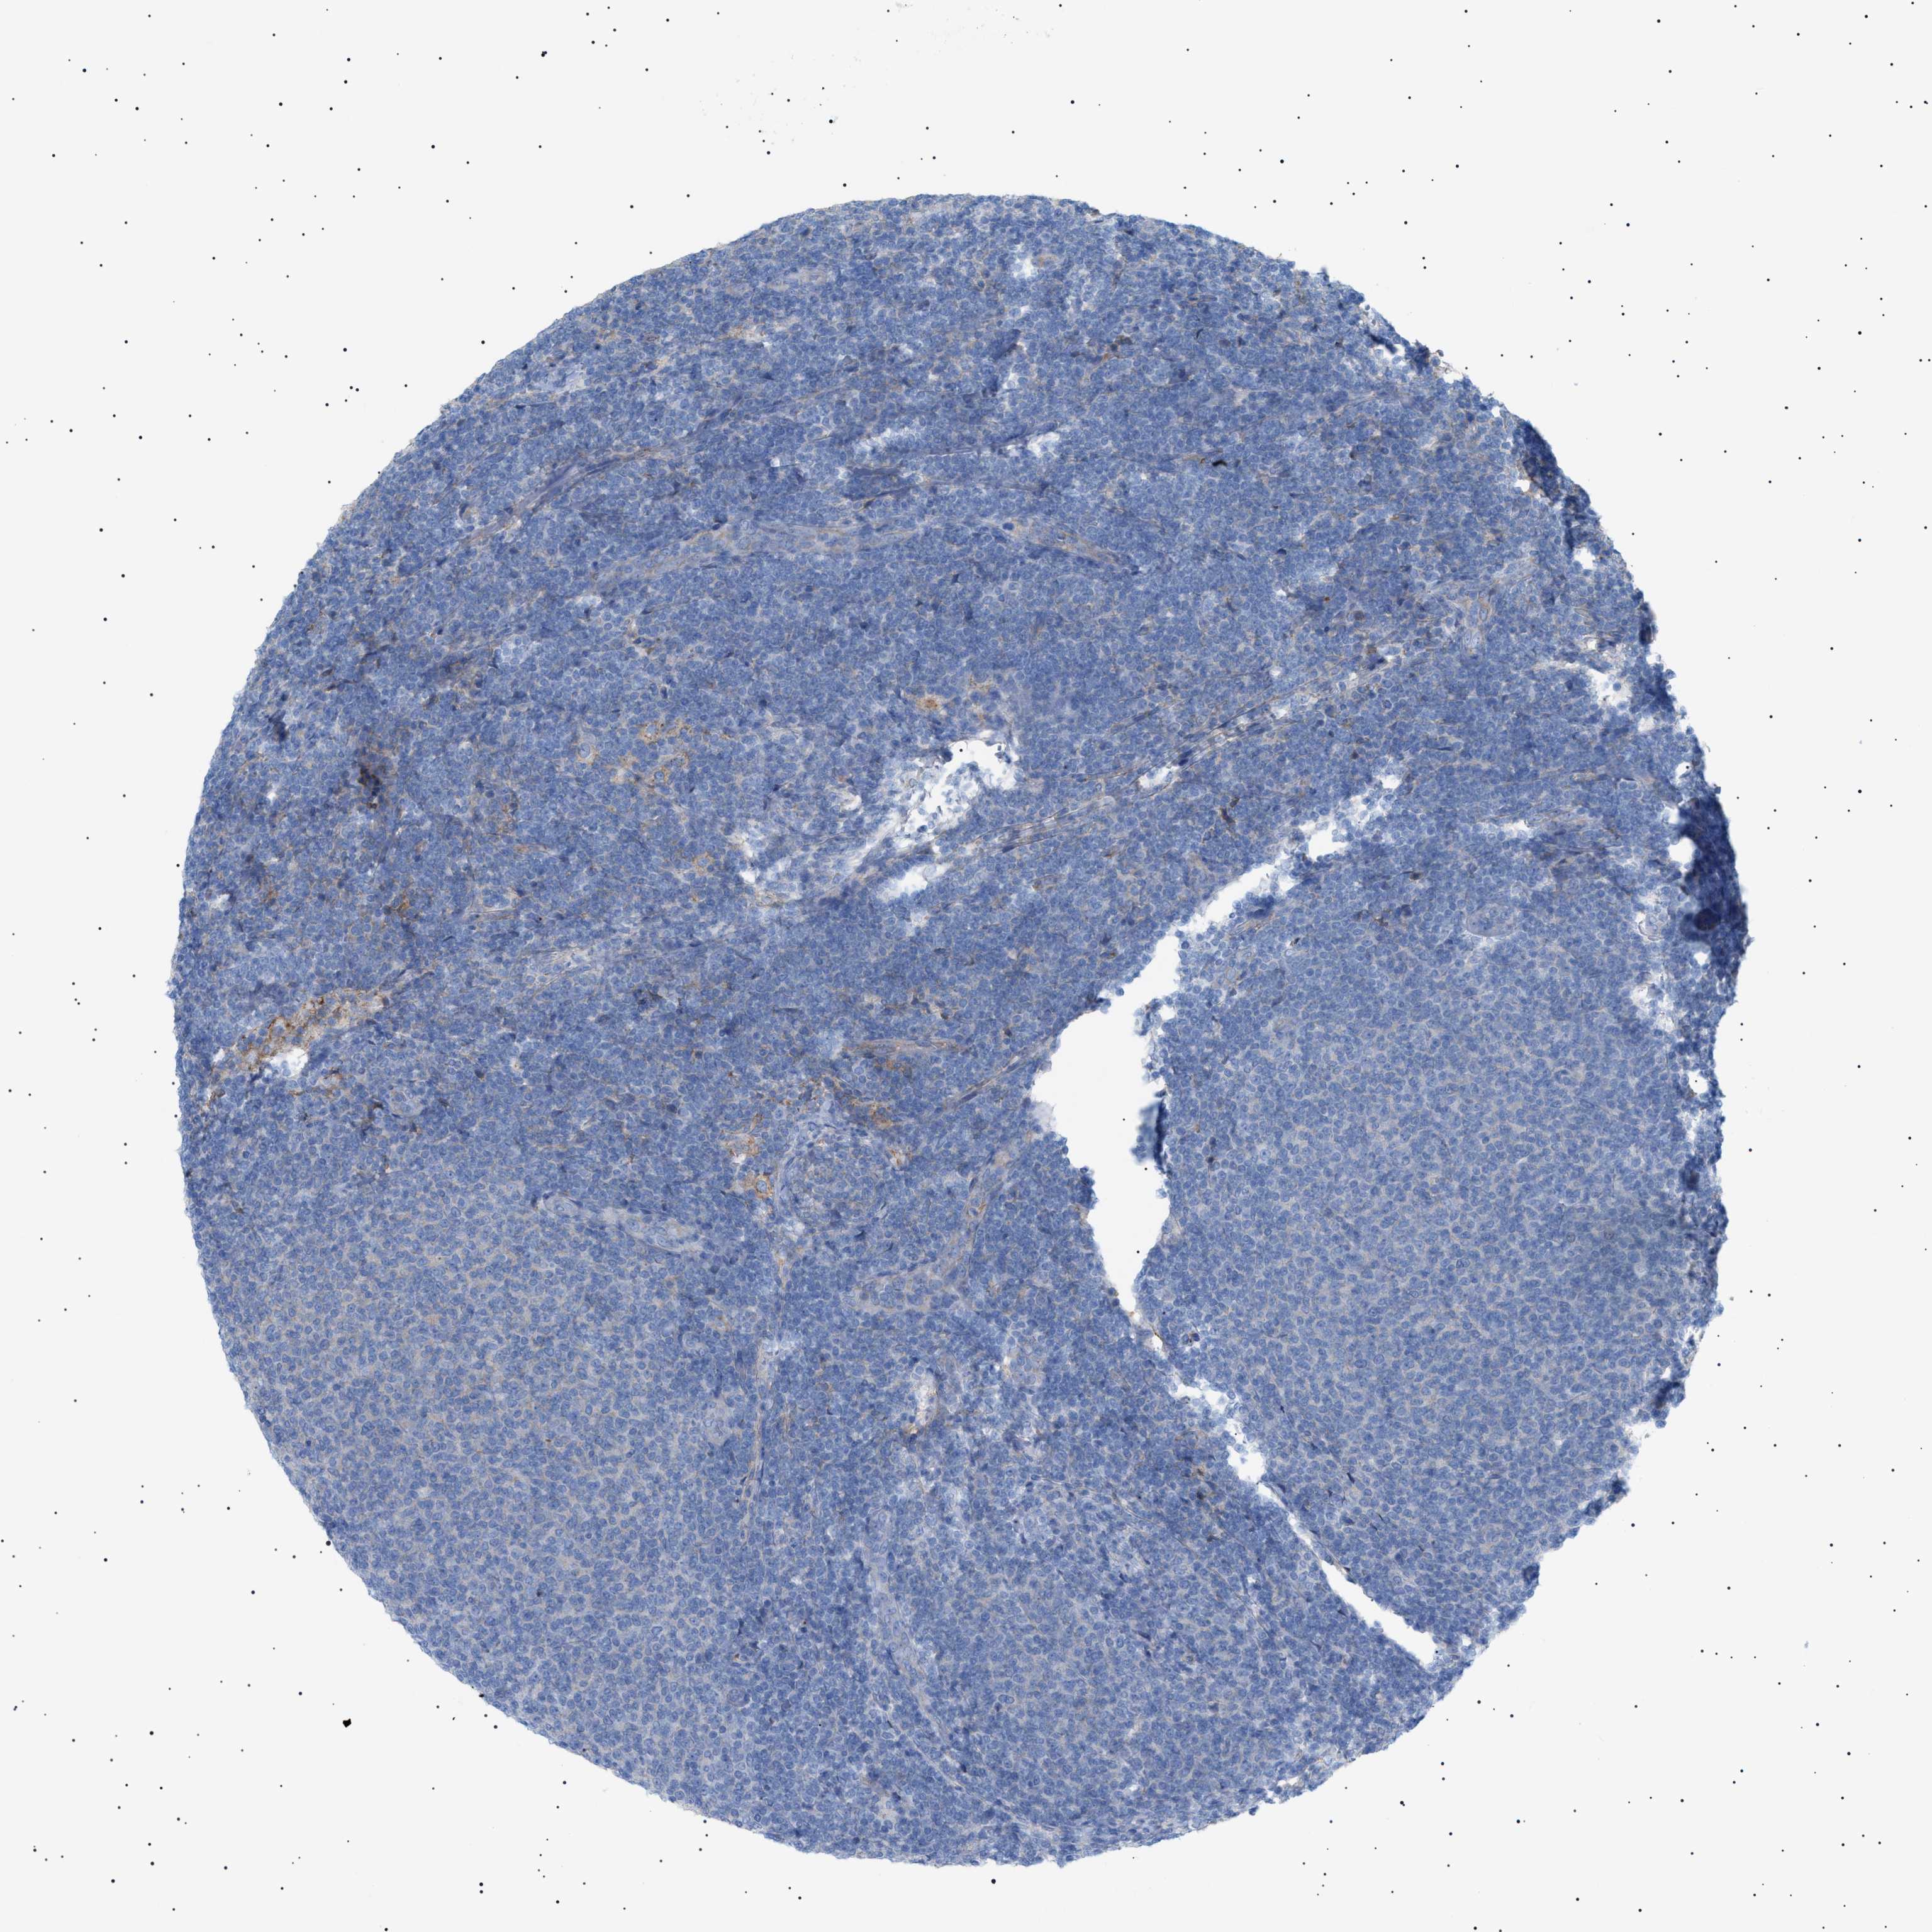

LYMPHOMA - Protein expressioni

A mouse-over function shows sample information and annotation data. Click on an image to view it in a full screen mode. Samples can be filtered based on level of antibody staining by selecting one or several of the following categories: high, medium, low and not detected. The assay and annotation is described here.

Antibody stainingi

Antibody staining in the annotated cell types in the current human tissue is reported as not detected, low, medium, or high, based on conventional immunohistochemistry profiling in selected tissues. This score is based on the combination of the staining intensity and fraction of stained cells.

Each image is clickable and will lead to virtual microscopy that enables deeper exploration of all samples and also displays staining intensity scores, fraction scores and subcellular localization as well as patient and tissue information for each sample.

Antibody HPA060604

Antibody CAB016072

Staining

High

Medium

Low

Not detected

Intensity

Strong

Moderate

Weak

Negative

Quantity

>75%

75%-25%

<25%

None

Location

Nuclear

Cytoplasmic/membranous

Cytoplasmic/membranous,nuclear

Malignant lymphoma, non-Hodgkin's type, Low grade

Malignant lymphoma, non-Hodgkin's type, High grade

Hodgkin's disease, NOS